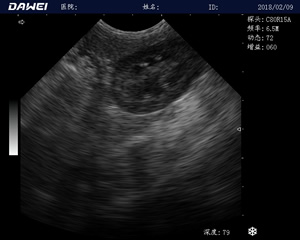

MT15獸用B超機適用探頭

適用對象:

牛羊馬豬犬貓及多種家禽、實驗動物、野生動物、及部分水生動物

應用范圍:

中小動物的肝、膽,脾、腎、膀胱、子宮、妊娠等各組織器官的檢查和病變的診斷